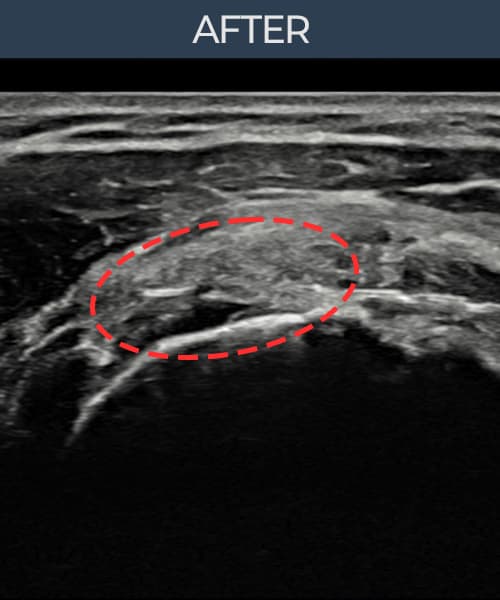

시술 전 초음파 측정 결과 파열 크기는 14mm × 7mm (힘줄 두께의 약 68% 결손)로 확인되었습니다. 시술 전 초음파에서 6개월 이상 방치로 인한 관절면측 회전근개 결손과 힘줄 위축 소견이 관찰되었습니다. 시술 후 초음파에서 파열 부위의 인대 연속성이 완전히 회복되었고, 인대 두께가 정상 범위로 복원된 것이 확인되었습니다.

70대 초반 남성 환자분으로, '나이 들면 으레 아픈 거겠지' 하며 6개월 이상 진통제로만 버티다 보행과 수면에 지장이 생겨서야 내원하셨습니다. 내원 당시 어깨를 90도 이상 올리기 어려운 상태였으며, 초음파 검사에서 관절면측 회전근개의 결손과 인대 위축이 상당히 진행된 것이 확인되었습니다. 고령임에도 전신 상태가 양호하고 파열이 관절면측에 국한되어 있어 비수술 축소봉합술이 적합하다고 판단하였습니다. 시술 후 보조기 착용 및 충분한 회복 기간을 확보하였으며, 65세 이후 조직 회복 속도를 고려해 재활 일정을 보수적으로 운영하였습니다. 시술 3개월 후부터 진통제 없이 수면이 가능해지셨고, 최종 경과 관찰에서 인대 연속성이 완전히 회복되어 일상 보행과 가벼운 운동이 가능한 상태가 되셨습니다.